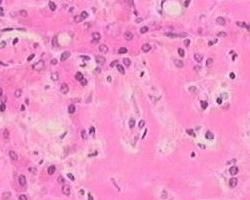

1.影像學檢查?缺乏特異性,超聲檢查主要改變為:肝臟體積增大,肝實質呈粗大點狀均勻回聲,門靜脈可增寬,有時可見腹水形成。CT主要表現為:肝大,肝臟瀰漫性低密度區,增強不明顯,肝內血管不移位(圖1,2)。